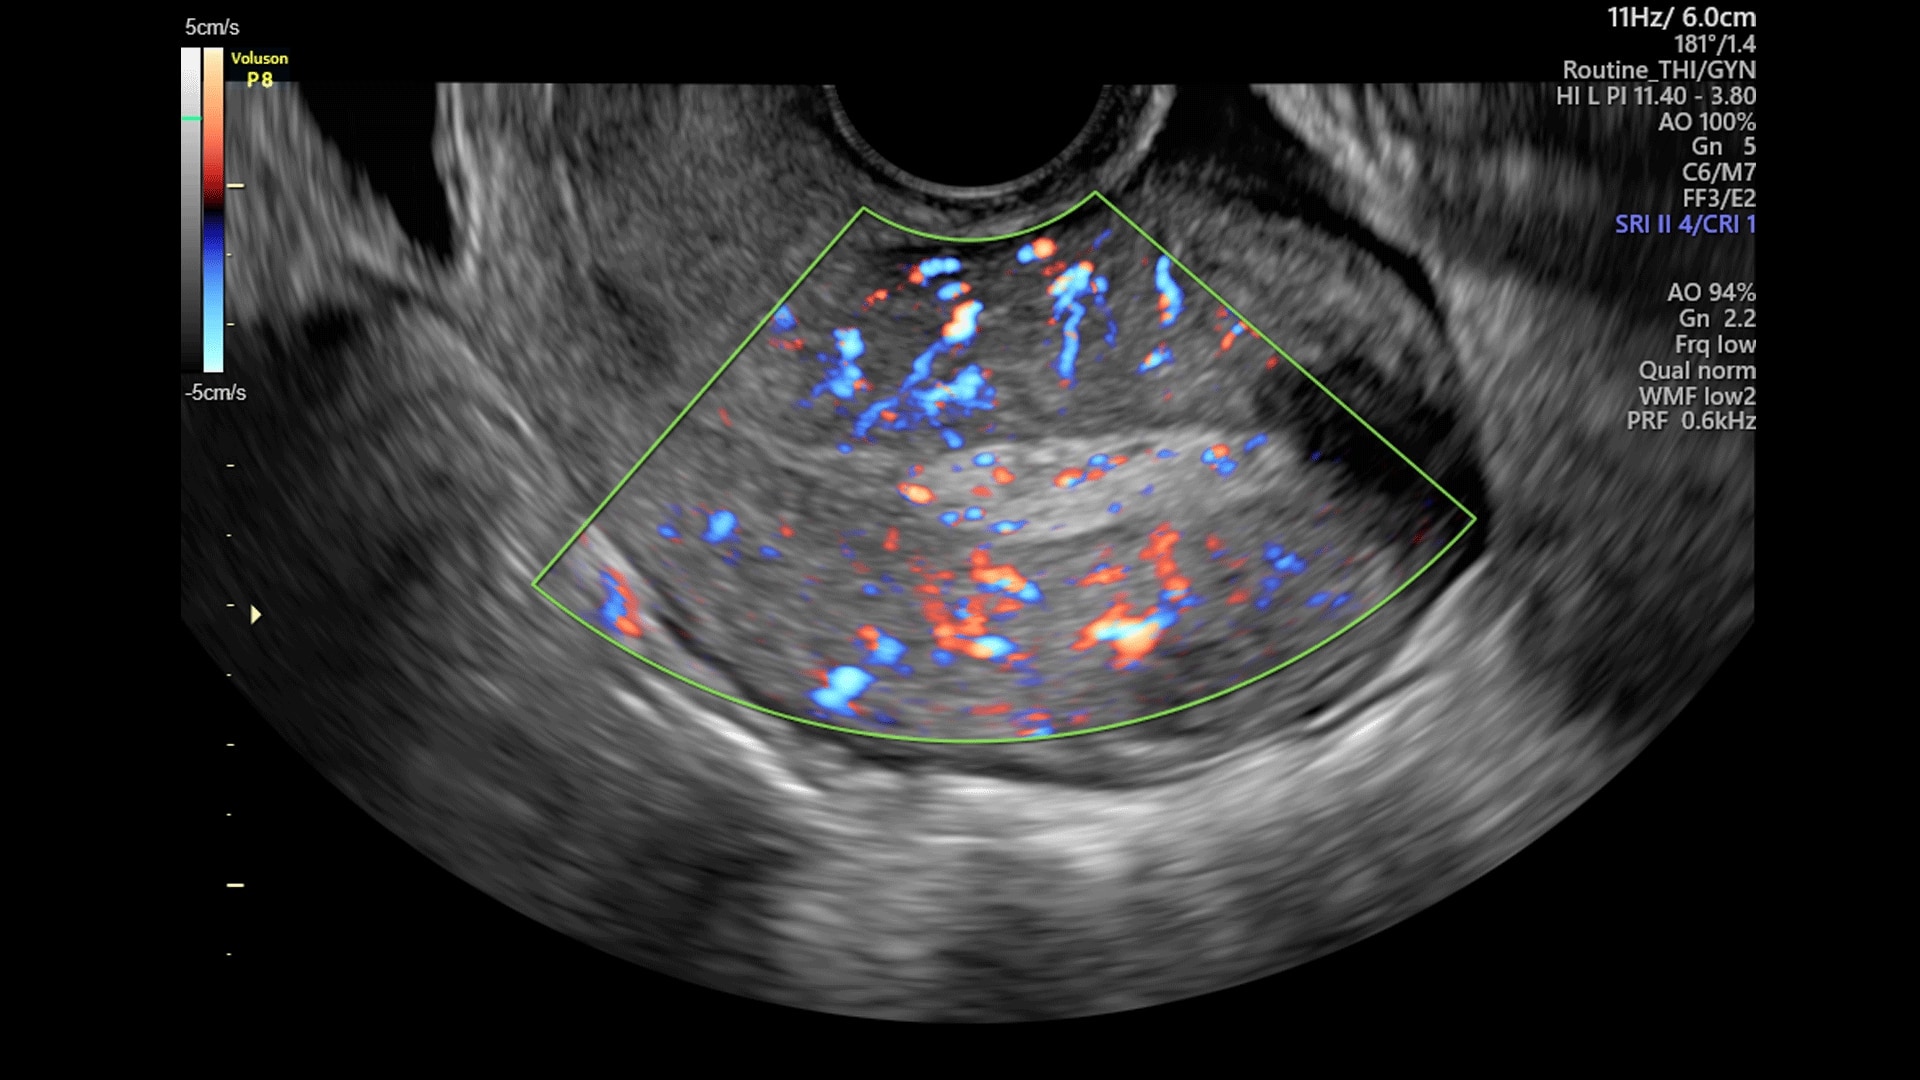

Simply place the probe to get the information you need. Built on Voluson Core Architecture, the P8 delivers excellent imaging across all types of patients and exams.

SonoAVC™follicle

SonoAVC™follicle automatically calculates the number, dimensions, and volume of hypoechoic structures in a volume sweep to help monitor patient follicles faster.